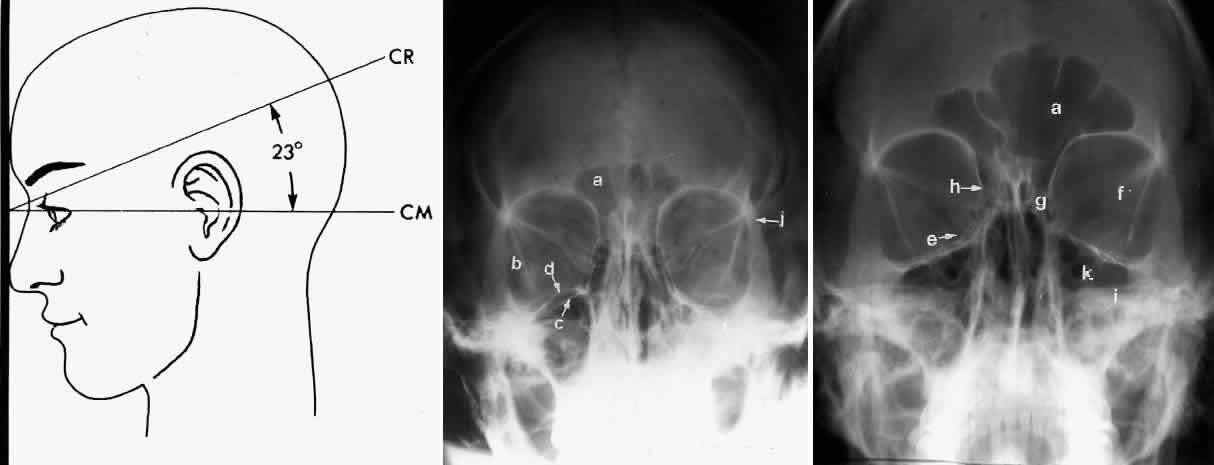

CALDWELL PROJECTION

In 1918 the evaluation of the frontal and ethmoid sinuses prompted Caldwell9 to describe a projection (Fig. 3) that eliminates the superimposition of the sphenoid bone on these paranasal sinuses. The patient is positioned with both the nose and forehead against the x-ray cassette while the x-ray beam is directed downward 15 degrees to 23 degrees to the canthomeatal line.5,6,9 This orientation also projects the petrous bones inferior to the orbit, thus avoiding obscuration of the orbital structures. As in the Waters view, the Caldwell view is a posterior-anterior projection. This excellent view of the frontal and ethmoid sinuses also allows good visualization of the orbital rims, greater and lesser sphenoid wings, lacrimal gland fossa, medial orbital wall, and both the superior and inferior orbital fissures.10 The innominate line is prominent in this view and represents the depression on the temporal surface of the greater wing of the sphenoid bone where it forms the medial wall of the temporal fossa or lateral wall of the orbit. This innominate line can be straight, end with a medial right angle turn, or continue inferiorly to form the outline of the pterygoid plate.8 A lack of continuity of the innominate line suggests a fracture of the lateral orbital wall.

Fig. 3. A. Schematic showing positioning for a Caldwell projection. (CM, canthomeatal line; CR, central ray) B. Radiograph of a Caldwell projection. The petrous ridge is positioned at the orbital floor. Detail of the orbital floor and maxillary sinus is blocked. C. The radiograph is taken at a steeper angle so the petrous ridge is now positioned lower within the maxillary antrum. (a, frontal sinus; b, innominate line; c, inferior orbital rim; d, posterior orbital floor; e, superior orbital fissure; f, greater wing of sphenoid;g, ethmoid sinus; h, medial orbital wall; i, petrous ridge; j, zygomatic-frontal suture; k, foramen rotundum) (A; Rao VM, Gonzalez CF: Plain film radiography and polytomography of the orbit. In Gonzalez CF, Becker MH, Flanagan JC [eds]: Diagnostic Imaging in Ophthalmology, pp 1–7. New York, Springer Verlag, 1986)